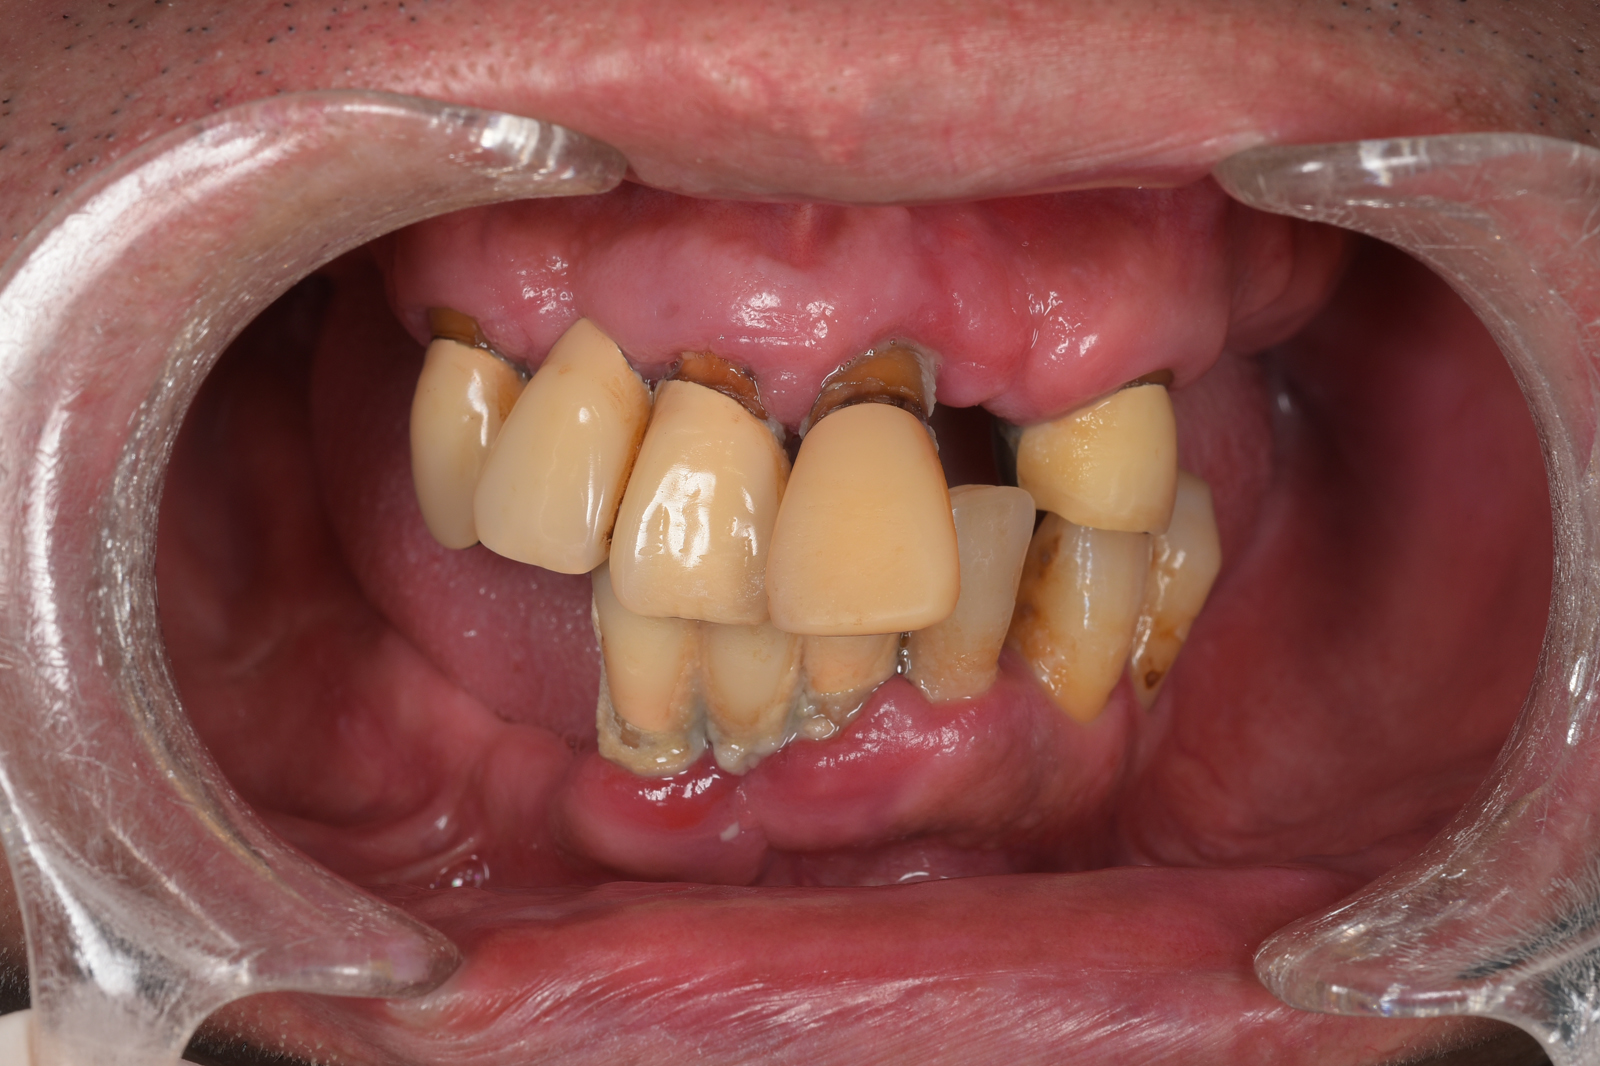

重度に進行した歯周病を治療するには、外科処置が必要になることがあります。特に歯医者嫌いの方にとっては、外科処置は大きなストレスになります。

そこで当院では、患者さんのストレスを軽減するために「睡眠無痛治療(静脈内鎮静法)」という治療を行っています。

睡眠無痛治療では、鎮静剤を点滴で投与します。患者さんはほぼ眠った状態のまま治療を受けられるので、痛みや不快感はまったくなく、気がついたときには治療が終わっています。

歯科恐怖症の方だけでなく、お口にものが入ると気分が悪くなってしまう「嘔吐反射」の強い方にもお勧めの治療法です。